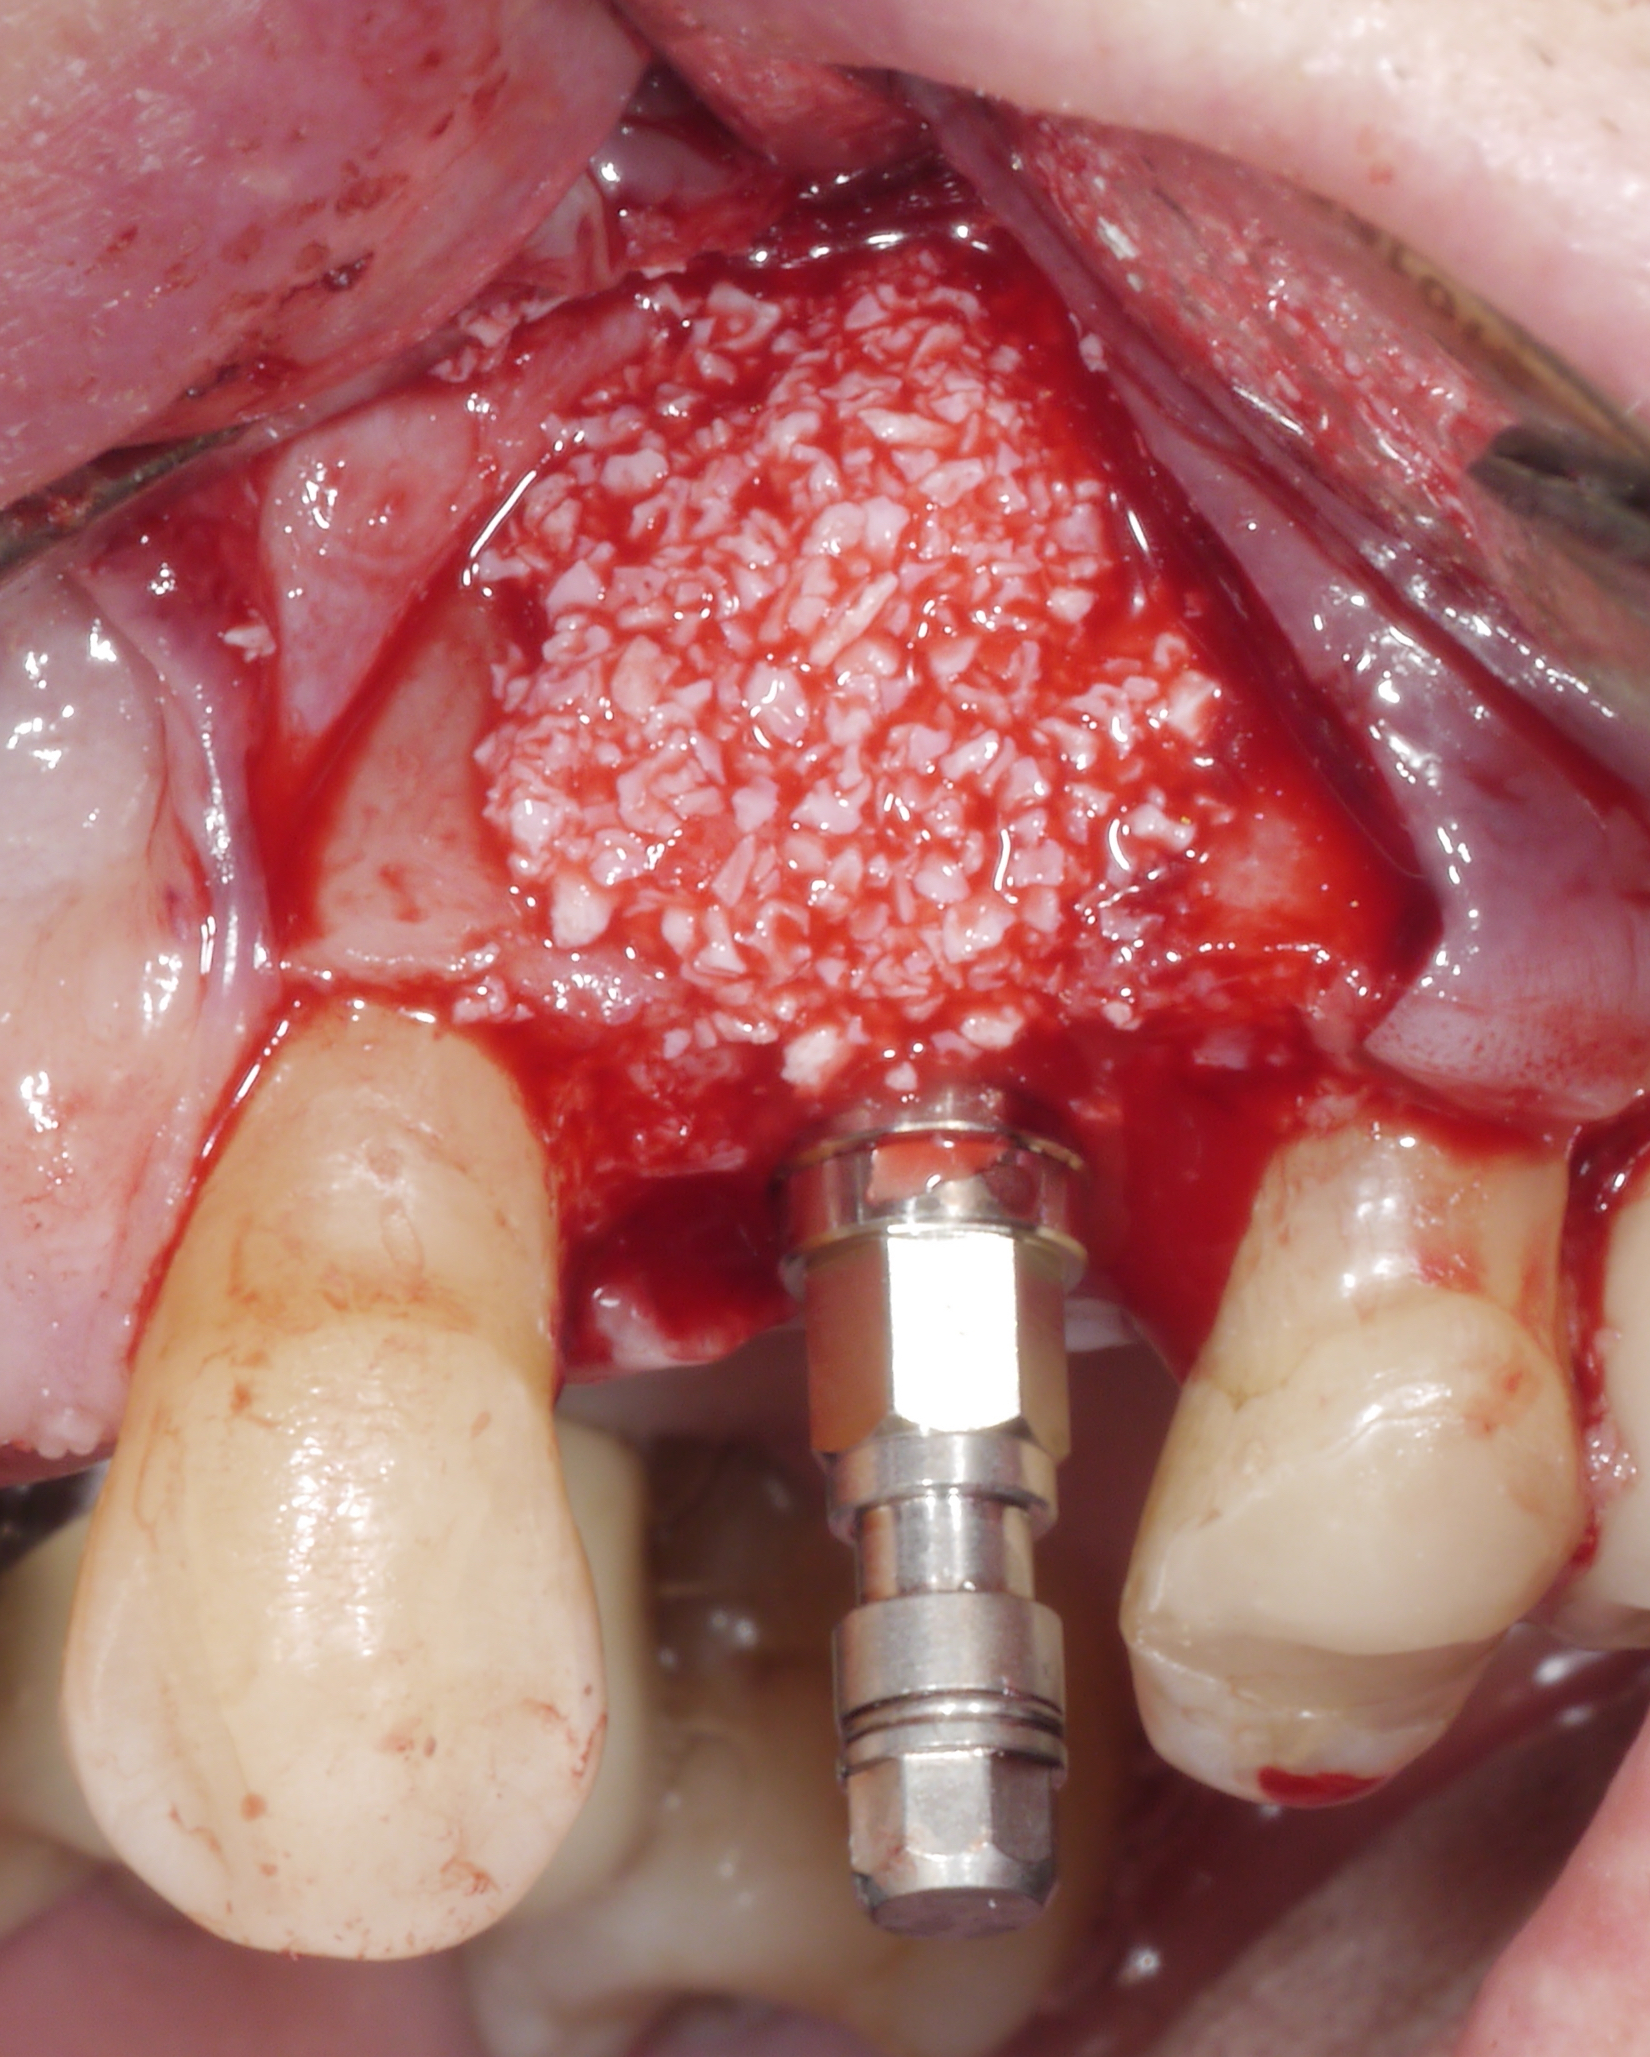

This 1-day hands-on course, using fresh human cadaver heads, provides insight into oral anatomy with relevance in oral surgical procedures. Main focus is the sinus lift procedure. Theoretical aspects on relevant anatomical issues and grafting procedures are presented in summary.

The hands-on parts cover the following procedures:

• Lateral window approach with rotary instruments

• Lateral window approach with piezosurgery

• Transcrestal approach with osteotomes

• Transcrestal approach with piezosurgery

• Transcrestal approach with osseodensification technique

• Transcrestal approach with a magnetic mallet

• Autogenous bone harvesting

Hands-on - Sinus Lift - Lateral window approach with rotary instruments / with piezosurgery

Hands-on - Transcrestal approach with osteotomes / with piezosurgery / with a magnetic mallet & Autogenous bone harvesting & Dissection of the sinus and other anatomical structures